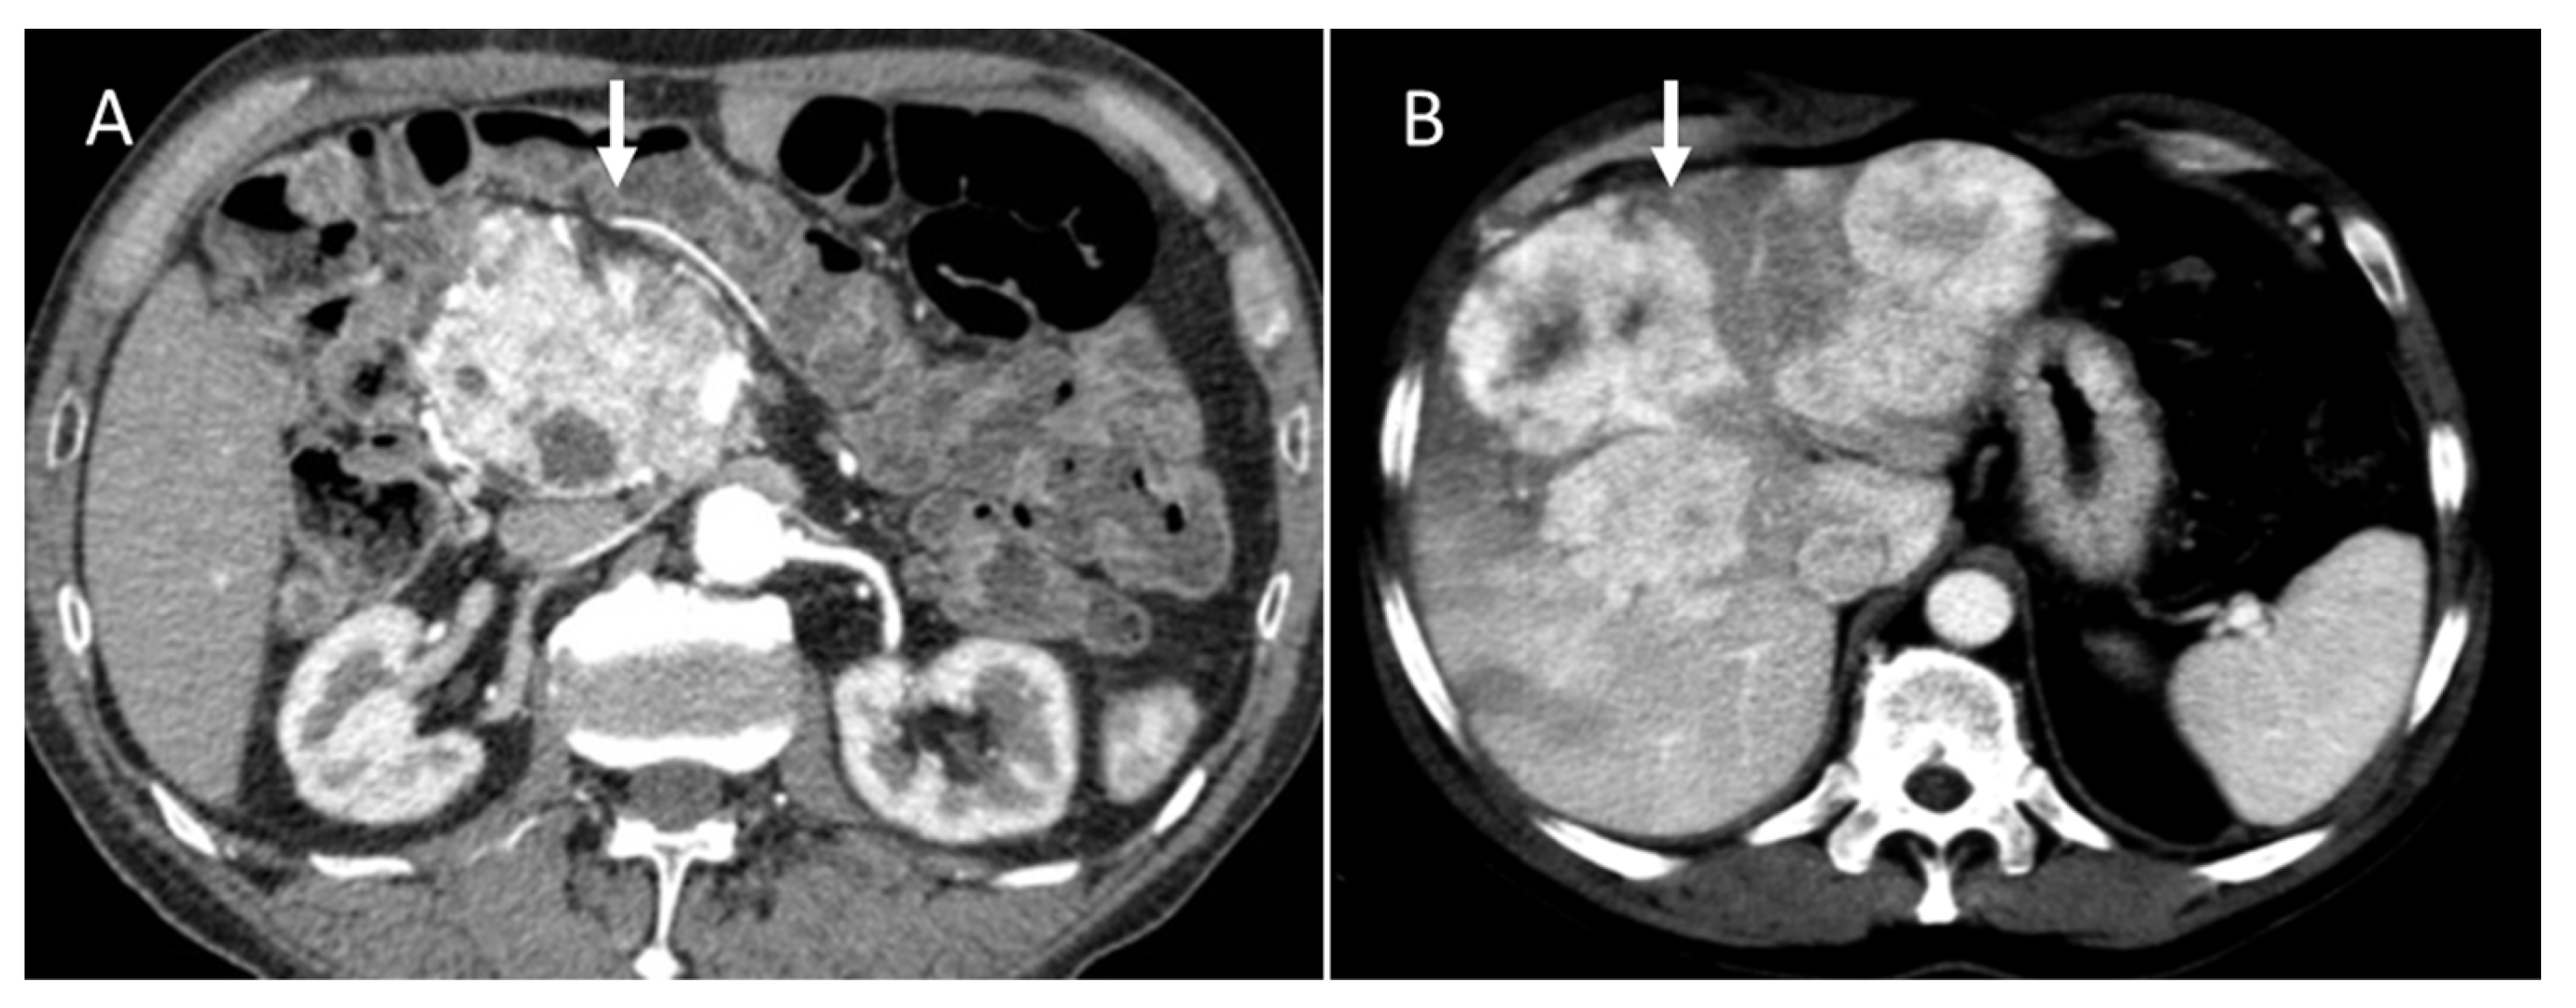

Figure 3.

CT evaluation during arterial phase of pancreatic NEN ((A): arrow) with liver metastases ((B): arrow).